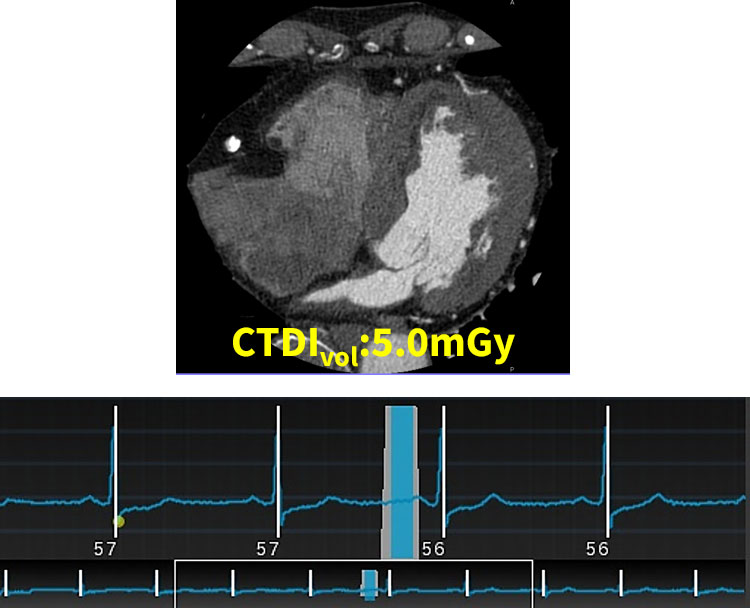

Auto Gating機能をオフにしてマニュアル設定を行うケースもあり、被曝をさらに低減するためにターゲット心位相を75%に限定したり(図1)、壁運動の情報が必要な場合には1心拍の部分をターゲット心位相以外で線量50%以下に設定することで(図2)、目的に応じた撮影を目指しています。

RevolutionApexElite_Minaminojunkanki03.jpg

(図1)ターゲット心位相75%のみCTDIvol:5.0mGy